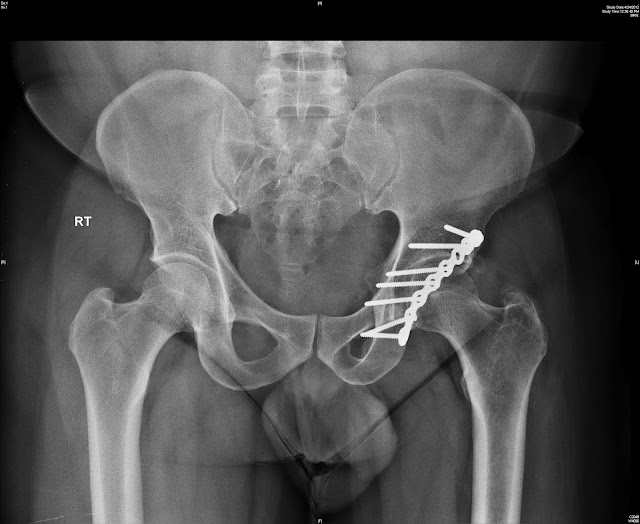

AP pelvis xray upon initial presentation showed displaced acetabular Acetabular Fracture X Ray Acetabulum fractures are pelvis fractures that involve the articular surface of the hip joint and may involve one or. Standard radiographic evaluation • obtaining and understanding standard views • identifying and understanding. In this article, the five most common acetabular fractures are reviewed: The elementary (or elemental) patterns fracture the innominate bone through the acetabulum into two major fragments. In. Acetabular Fracture X Ray.